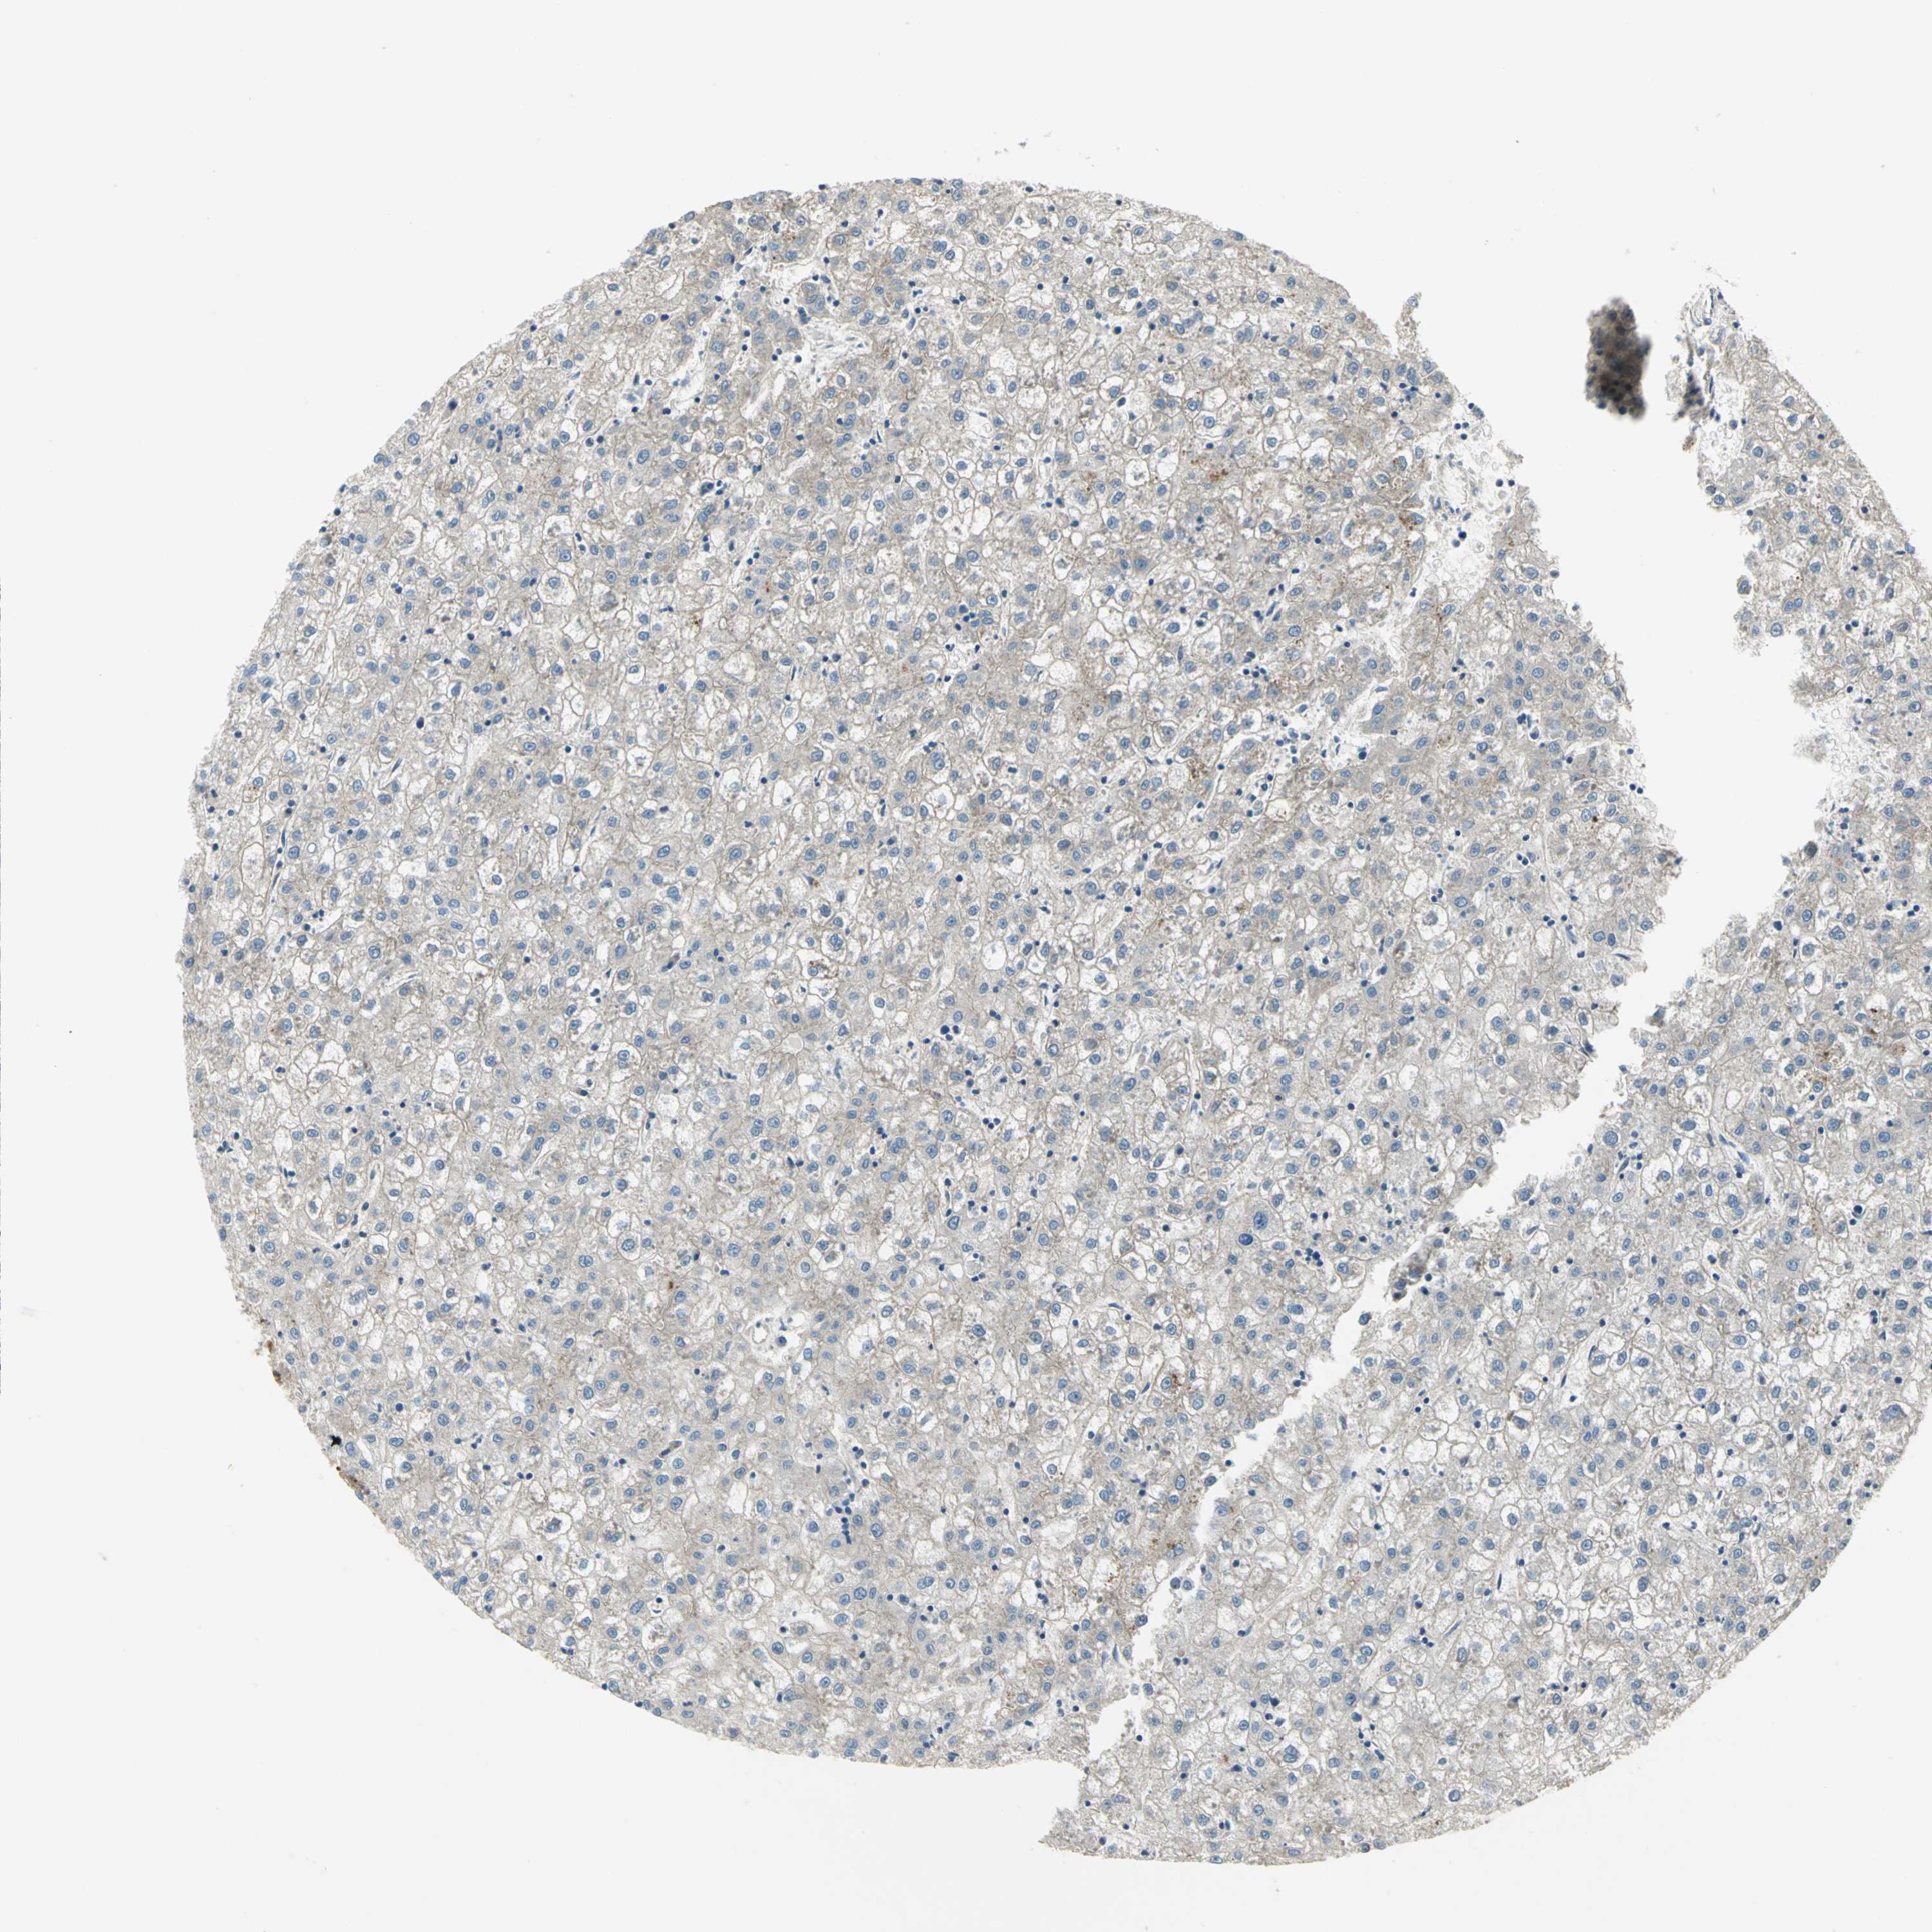

LIVER CANCER - Protein expressioni

A mouse-over function shows sample information and annotation data. Click on an image to view it in a full screen mode. Samples can be filtered based on level of antibody staining by selecting one or several of the following categories: high, medium, low and not detected. The assay and annotation is described here.

Note that samples used for immunohistochemistry by the Human Protein Atlas do not correspond to samples in the TCGA dataset.

Antibody stainingi

Antibody staining in the annotated cell types in the current human tissue is reported as not detected, low, medium, or high, based on conventional immunohistochemistry profiling in selected tissues. This score is based on the combination of the staining intensity and fraction of stained cells.

Each image is clickable and will lead to virtual microscopy that enables deeper exploration of all samples and also displays staining intensity scores, fraction scores and subcellular localization as well as patient and tissue information for each sample.

Antibody HPA064946

Antibody CAB005050

Staining

High

Medium

Low

Not detected

Intensity

Strong

Moderate

Weak

Negative

Quantity

>75%

75%-25%

<25%

None

Location

Nuclear

Cytoplasmic/membranous

Cytoplasmic/membranous,nuclear

Carcinoma, Hepatocellular, NOS

Cholangiocarcinoma